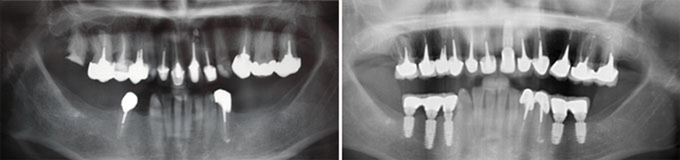

J’ai une maladie des gencives et mes dents tombent les une après les autres, je refuse un appareil que je serais obligé d’enlever

Solution : on va traiter les dents qui sont récupérables et remplacer les autres par des implants.

Implants multiples pour éviter les bridges et redonner des dents individuelles au patient avec traitement d’une maladie parodontale.

Implants multiples pour éviter les bridges et redonner des dents individuelles au patient. État final.